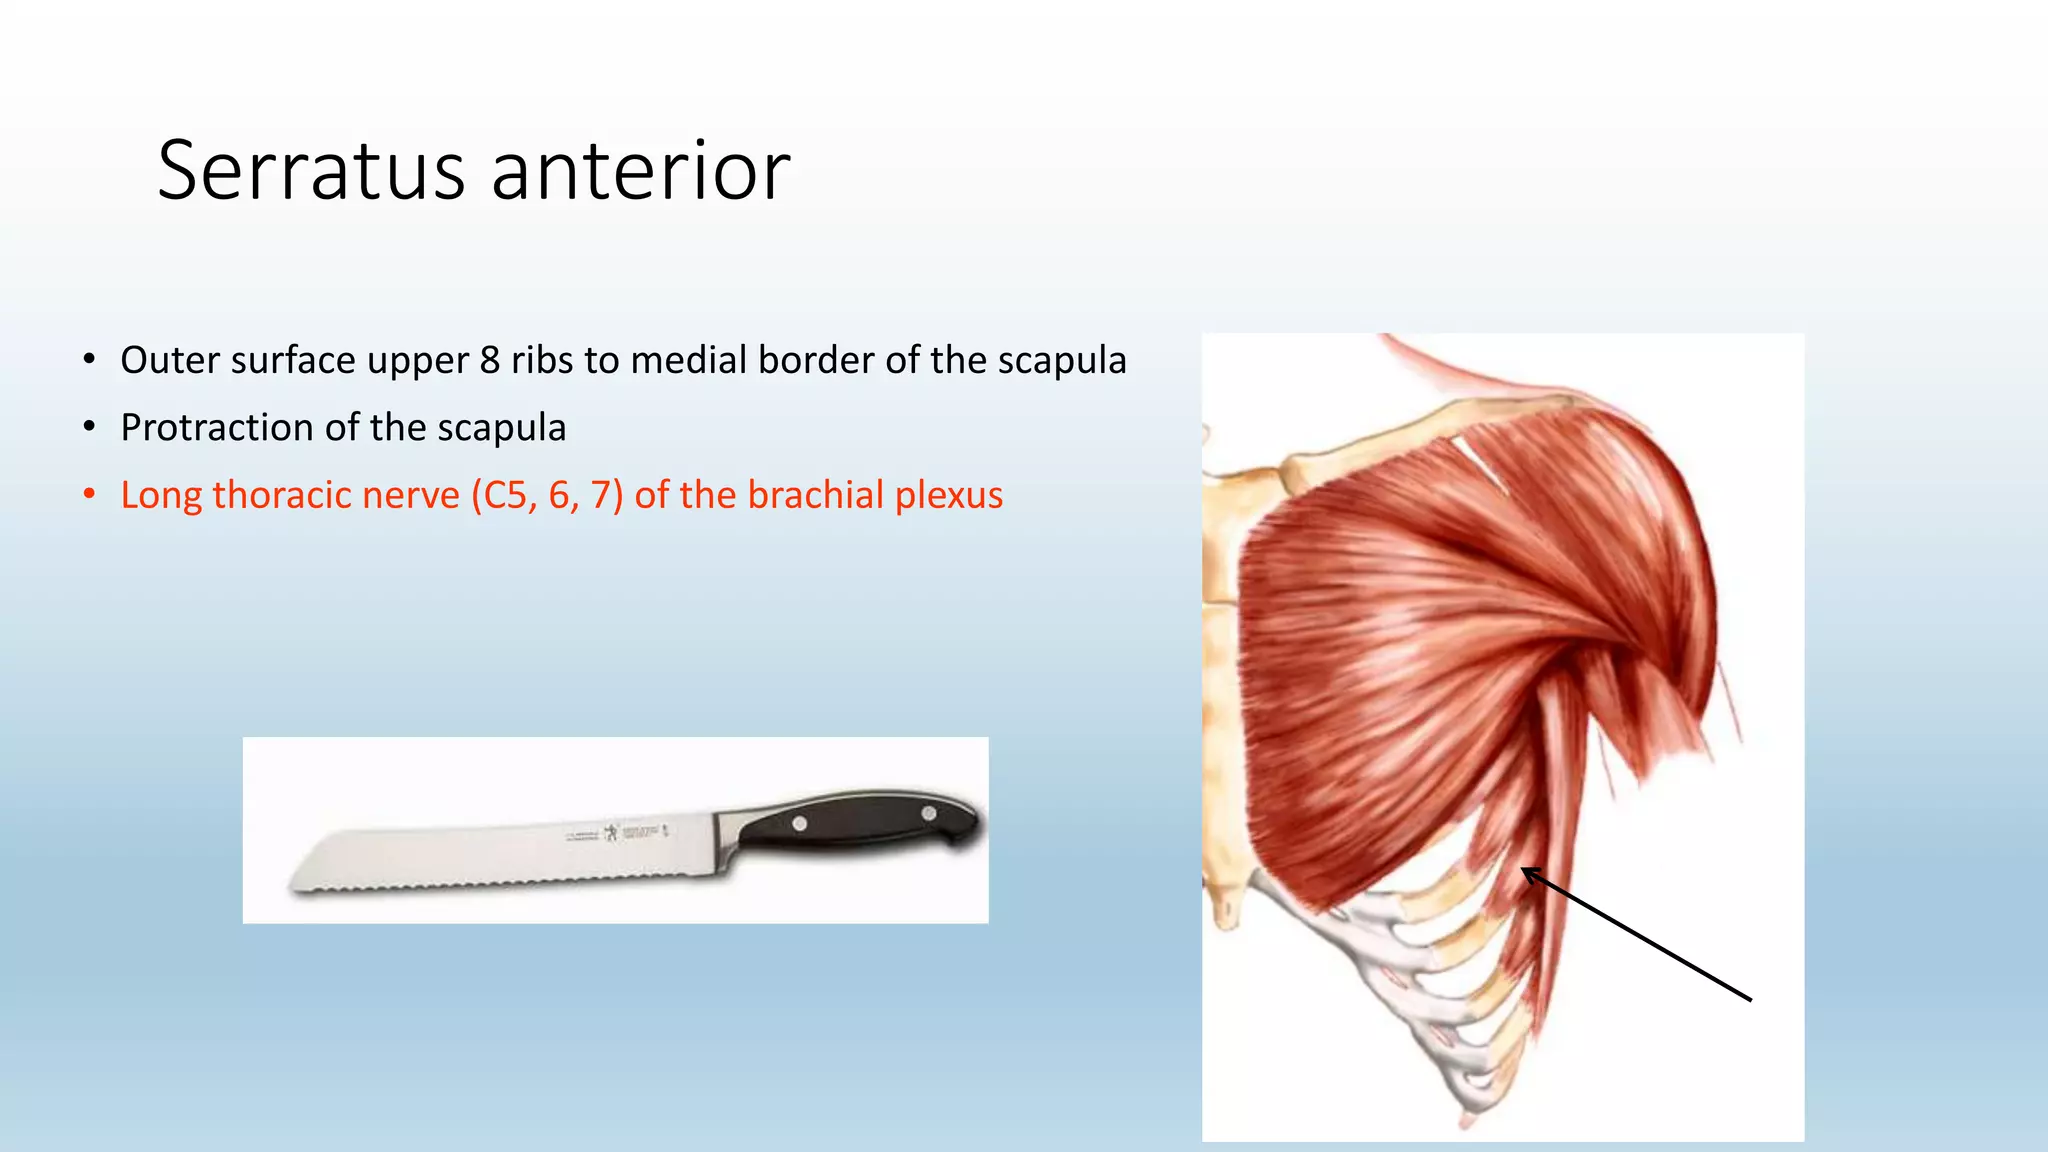

The document summarizes an anatomy revision session on the upper limb. It discusses various muscles of the upper limb including their origins, insertions, innervations and functions. Key muscles covered include the pectoralis major and minor, serratus anterior, deltoid, biceps brachii, brachialis, coracobrachialis, and triceps. It also discusses the rotator cuff muscles and muscles of the forearm including flexor carpi ulnaris and radialis. The session aims to help students identify upper limb muscles and understand their relations to nerves.